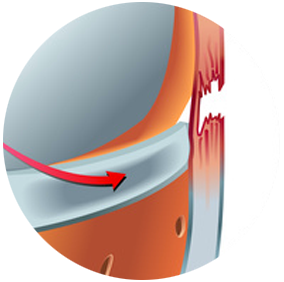

Prothèse unicompartimentale du genou

Le but de la prothèse unicompartimentale du genou est d’enlever les zones d’os et de cartilage partiellement usées par l'arthrose et de les remplacer par des pièces artificielles ayant la mêmes formes.